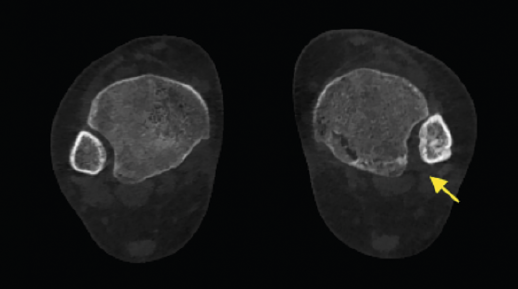

- Valoración rotacional del primer radio y desplazamiento de los sesamoideos. Valoración de la deformidad y rotación del primer radio, así como el desplazamiento lateral de los sesamoideos (Figura 9).

Figura 9. Se aprecia un desplazamiento lateral de los sesamoideos en deformidad del hallux valgus.